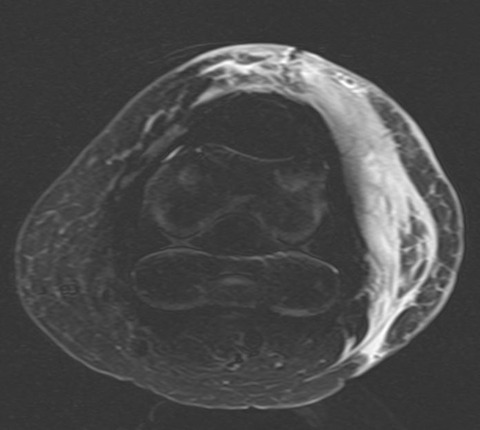

そこでMRIを施行すると、大腿骨・脛骨・膝蓋骨とも明らかな骨折は認めませんでした。これで自信をもって患者さんに説明できます。

一方、現在の疼痛の原因は膝関節側方の皮下に存在する広範な血種のようです。更に自信をもって患者さんに説明できます。人工関節周囲骨折を疑った場合には MRIが有用ですね!